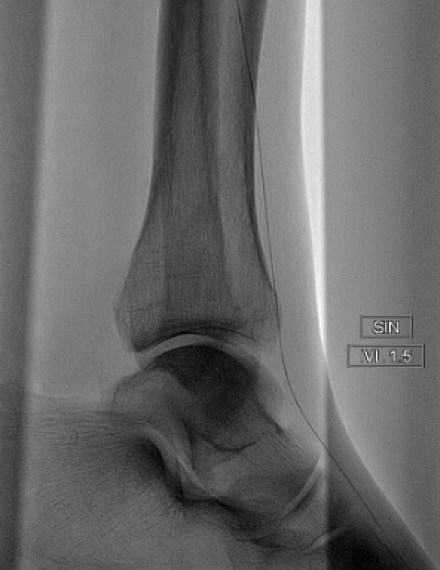

Pre-procedure

Baseline angio shows a total occlusion of the anterior tibial artery (ATA), with a diffuse lesion of 30 cm length. Ankle-brachial index (ABI) pre procedure: 0.30. -